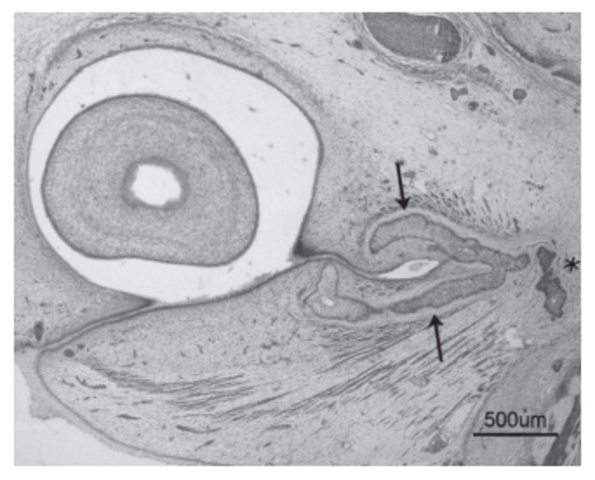

DESARROLLO DEL NERVIO ÓPTICO

- Los axones de las células ganglionares de la retina neurosensorial crecen hacia el pedículo o tallo óptico. De esta manera, la cavidad del tallo se va obliterando. La aparición de los axones en la futura papila se observa en embriones de 16 mm de longitud GL; 6,5 semanas de desarrollo, 44 días. Las células del pedículo óptico rodean cranealmente a estas fibras y a la arteria hialoidea

Día 37 de desarrollo; comienza el cierre de la hendidura embrionaria, debido al crecimiento de los bordes del pedículo óptico. Durante la semana 7 del desarrollo, se observa el quiasma óptico. En la región de la futura papila aparece una acumulación de glioblastos, esbozo de la membrana limitante de Elschnig y del menisco central de Kuhnt, separando las fibras del nervio óptico del vítreo secundario

A los 23 mm de longitud GL (51 días de desarrollo), la arteria hialoidea presenta en su inicio de recorrido intraví- treo una lámina limitante de glioblastos (papila de Bergmeister).

En la región posterior del nervio (retroescleral) aparecen numerosos vasos y tejido conjuntivo que penetra desde la envoltura pial en la semana 12 de desarrollo.

En los meses 5-6 de desarrollo se completa la vascularización del nervio óptico y los vasos que forman el círculo arterial de Zinn-Haller muestran anastomosis. Durante el séptimo mes se forma la fibrosa de la lámina cribosa a la vez que comienzan a desarrollarse los vasos retinianos.